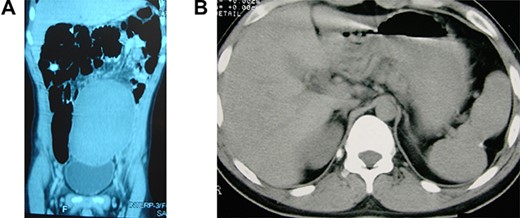

Wandering and twisted splenomegaly. (A) CT scan of the abdomen showing a displaced ectopic spleen in the left flank and pelvic region, characteristic of a wandering spleen. Observe the absence of the spleen in the left hypochondrium. (B) The spleen after detorsion and splenopexy in the left hypochondrium. Observe the reduction of the spleen to a normal size four years after the splenopexy.

The patient had an uneventful recovery and was discharged from the hospital on the second postoperative day. The most significant body growth occurred during the first 9 months after the surgery, and at 18 years of age, he had grown to 183 cm in height, similar to his family size. Together with the body height, all sexual characteristics were improved to normal aspects short time after the splenopexy. All laboratory exams had returned to normal, including a platelet count of 280 × 103/μl, a white blood cell count of 6.4 × 103/μl and a hemoglobin level of 14.9 g/dl. A new CT image demonstrated an almost normal spleen (14 × 12 × 10 cm) with no splenic or abdominal disorder (Fig. 1B). After four years, the patient is still in good health with a normal life, with no complaint related to the surgical procedure.